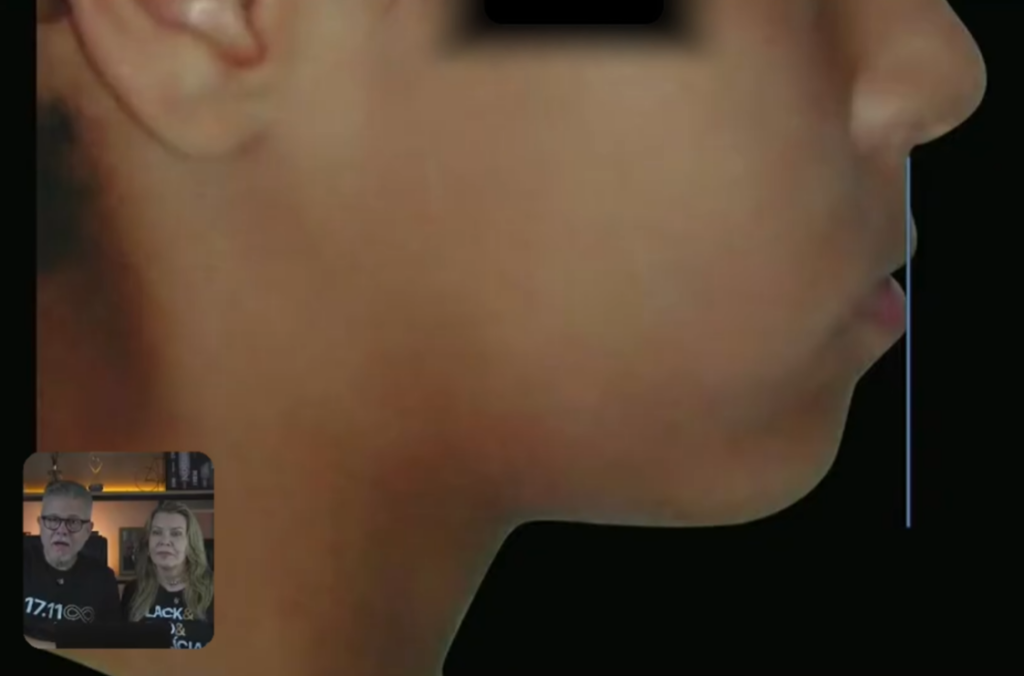

A gente está percebendo aqui que esse paciente, olha a face dele:

Aparentemente é um paciente normal.

Ele pode até ter ali uma linha que é o pescoço um pouquinho maior, mas eu não vejo tanta diferença.

Está bonita a face dele.

Então quando a gente olha:

O paciente está com a face bonita;

Só um ponto, aqui na face, quando a gente faz aquela vertical verdadeira:

E aí, muitas pessoas devem estar perguntando: “não, mas o lábio inferior, ele deveria estar um pouquinho mais para trás”.

Não, ele está tocando nessa linha.

Me parece que o lábio superior que está um pouquinho mais para trás.

Por que? Inclinação de incisivos.

Tanto o incisivo inferior está vestibularizado, quanto o incisivo superior está lingualizado, causando essa diferença no lábio que vai ficar corrigida depois do tratamento.